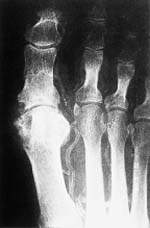

Гангрена Пальцев Стопы Фото